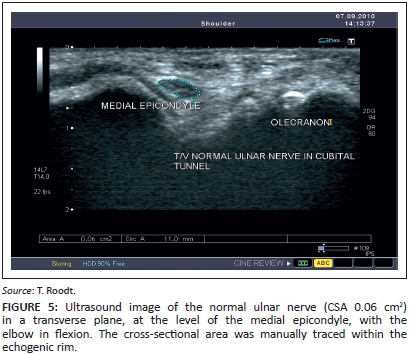

The probe was then rotated through 90° into the transverse plane until the nerve appeared as an oval or round structure (Figure 5). To obtain this image, the medial aspect of the transducer (side of the marker on the transducer) was placed at the medial epicondyle and the lateral aspect of the transducer on the olecranon process (Figure 6).

Area measurements were performed on a transverse section of the nerve during flexion, by using the manual free-hand tracing method. Three successive CSA measurements were obtained within the echogenic rim of the ulnar nerve (Figure 5) at:

1. the level of the medial epicondyle of the elbow